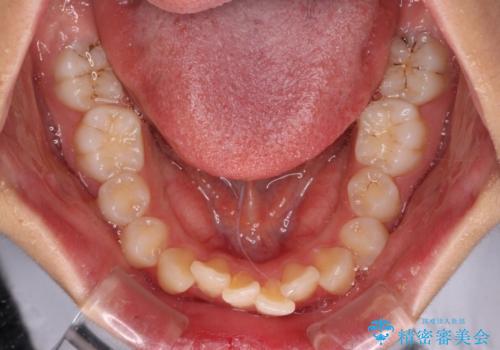

舌の突出癖などにより、上下前歯の間に指が入るくらい隙間のできる状態でした。

下顎は叢生があったため、上下左右の第一小臼歯4本を抜歯し、更には口元の突出感を大きく改善させるために、上顎臼歯を後方に移動させるための補助装置をしようし、ワイヤー装置にて矯正治療を行うこととしました。